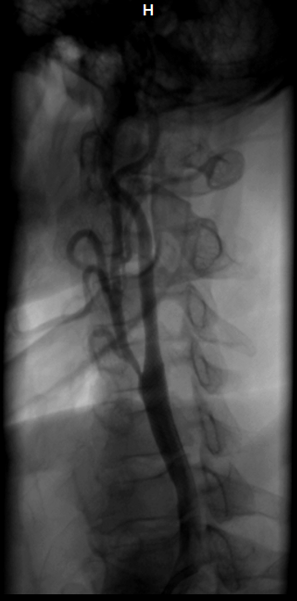

5.2 Chụp và can thiệp mạch máu ngoại biên:

Nong bóng, đặt stent giúp giải quyết các tổn thương hẹp, tắc ĐM cảnh gây thiếu máu não, ĐM thận gây suy thận, ĐM chi gây thiếu máu nuôi chi… Đặt stent graft động mạch chủ ngăn ngừa vỡ phình động mạch chủ lớn…

Trước can thiệp Sau can thiệp

Một trường hợp hẹp nặng ĐM cảnh trong giải quyết tốt bằng Wallstent